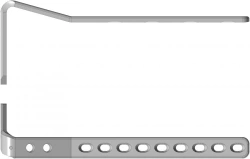

Non-Sterile Titanium Alloy Heel Reconstruction Plate with Angular Stability

US$150-540

Material:

Titanium alloy

Material:

Titanium alloy

HEALTH+ LLC 🇷🇺